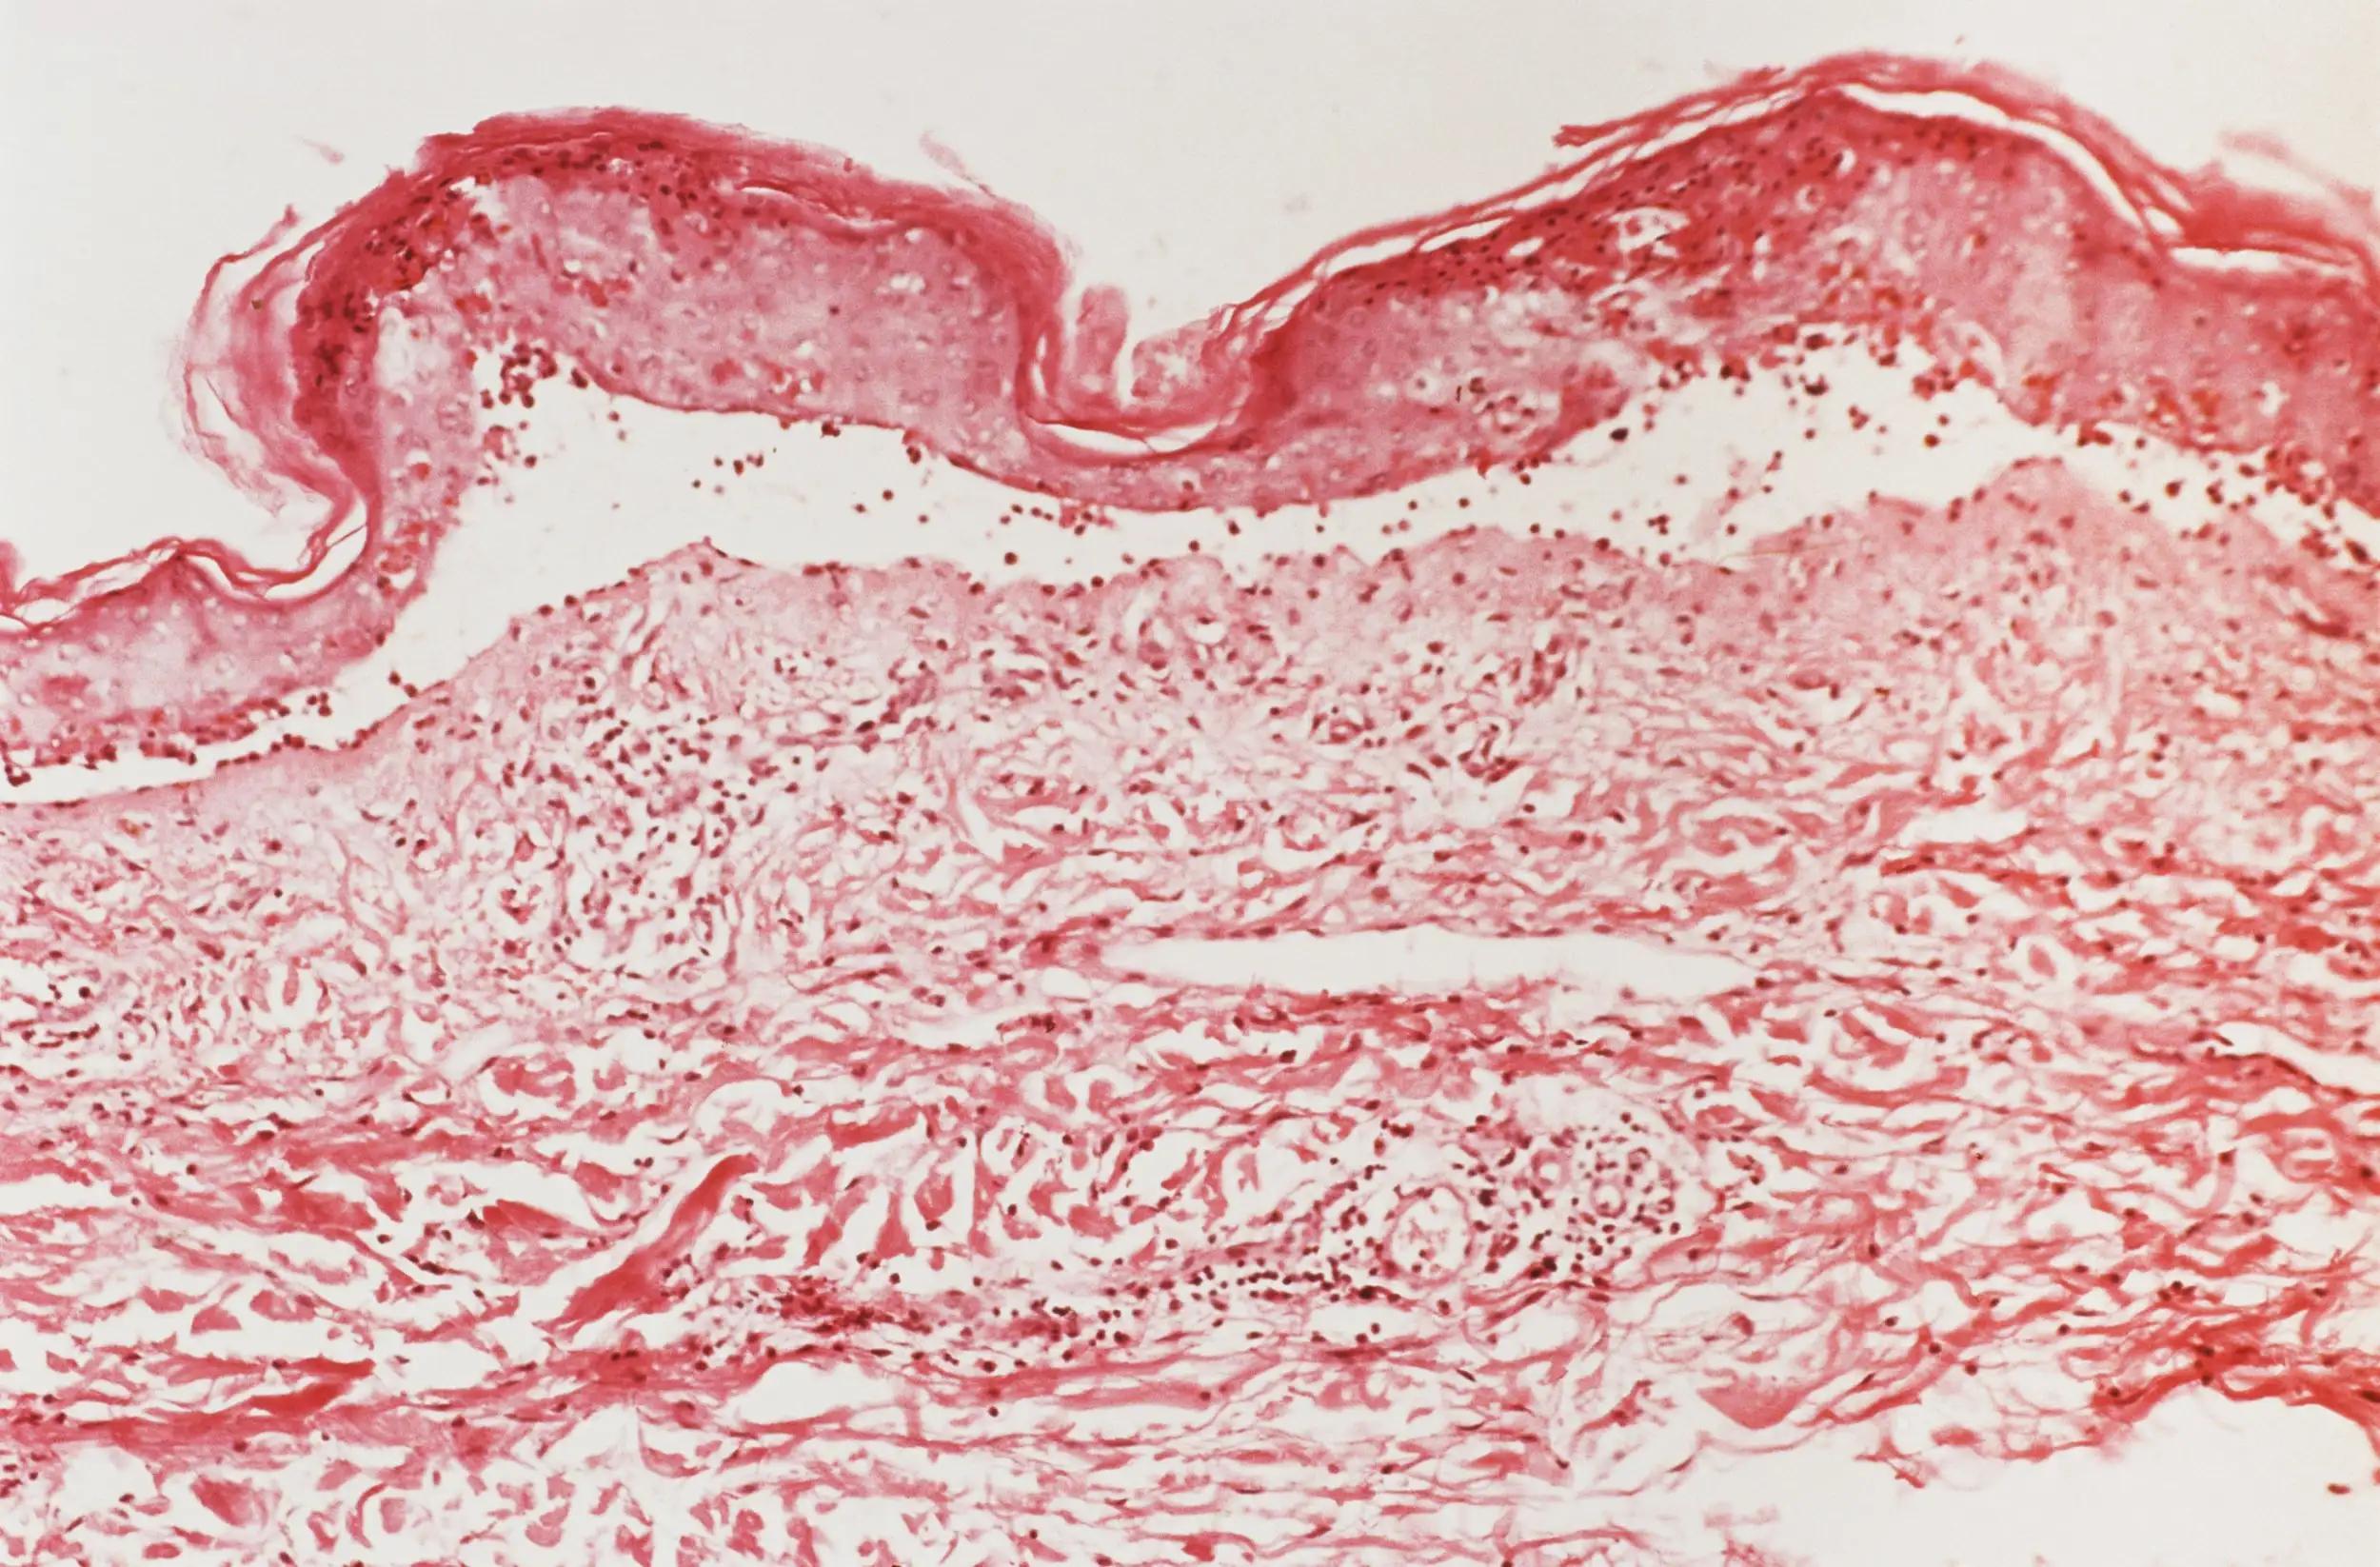

A micrograph showing the top layer of skin starting to detach in someone with toxic epidermal necrolysis

Biophoto Associates/Science Photo Library